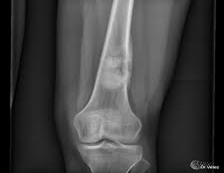

1. Rayos X

2. Resonancia magnética

3. TAC contrastado

4. Gammagrafía Ósea

Se usa una amplia gama de técnicas de adquisición de imágenes para poder ver dentro del cuerpo y determinar el alcance de un sarcoma óseo y establecer la presencia o ausencia de enfermedad metastásica distante.